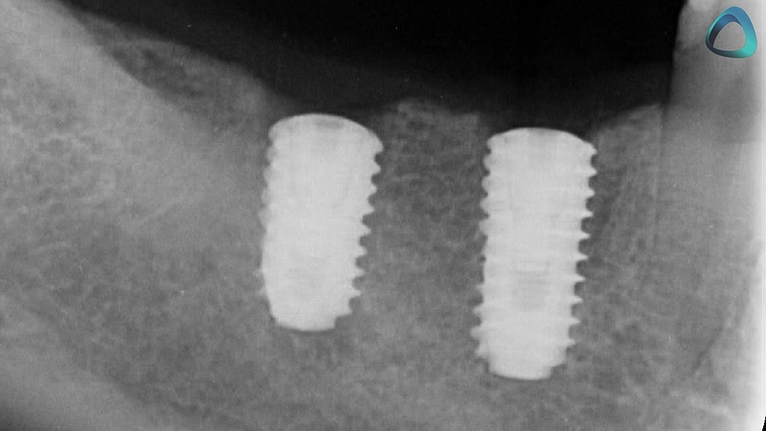

Using X Guide for the first time ever, we placed two implants for this patient in less than 40 minutes, which is what the postoperative x-ray looks like, perfectly parallel. Something that would not be achievable freehand.